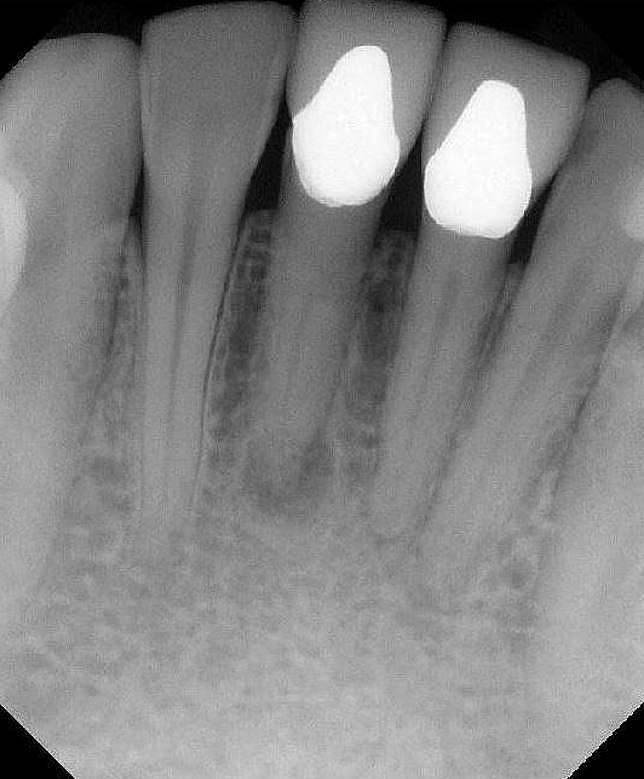

X-Ray 4: How many caries are present?

(Required)

X-Ray 4: How many PAP's are present?